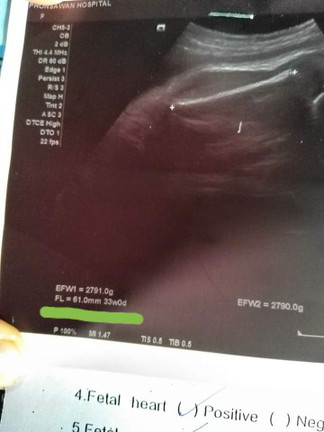

มีลูกใครน้ำหนักดีเท่าบ้านนี้บ้างคะตอนไปชาวด์33วิคน้องหนัก2790กรัมเเร้วจนคุนหมอทักว่าโอ้โห้เเมาตัวเล็กๆเเต่ลูกไม่เล็กเรยไอ่ต้าวอ้วง

ตอนไปชาวด์33วิคค้ะตอนนี่38+3ยังไม่รุ้ว่าน้องหนักกี่โล😘